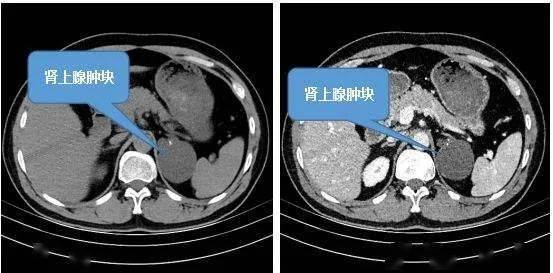

111大结节样增生伴肾上腺显著增大

图片尺寸1318x926